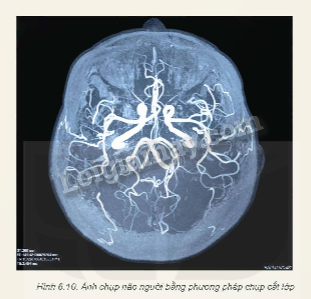

Nguyên lí chụp cắt lớp: Để chuẩn bị chụp, bệnh nhân được nằm trên bàn trượt và được đưa vào trong máy chụp. Bàn trượt được điều khiển để vùng cần chụp của bệnh nhân nằm giữa vùng đầu dò và ống phát tia X.

Trong quá trình chụp, ống phát tia X quay xung quanh bệnh nhân. Các chùm tia X sau khi xuyên qua cơ thể bệnh nhân được ghi bởi hệ thống đầu dò tia X. Dữ liệu thu được từ hệ thống đầu dò tạo ra một loạt ảnh X - quang hai chiều ở nhiều góc độ khác nhau.